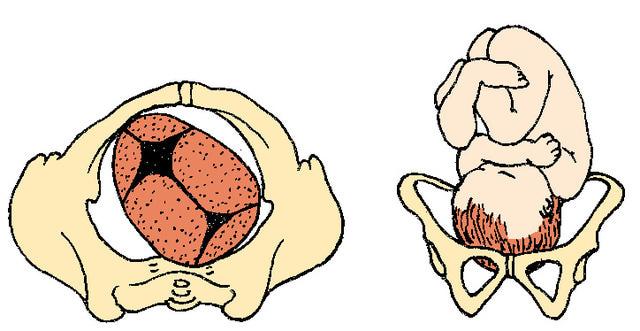

Complete Breech

What are the two footling breech positions?

single footling

double footling